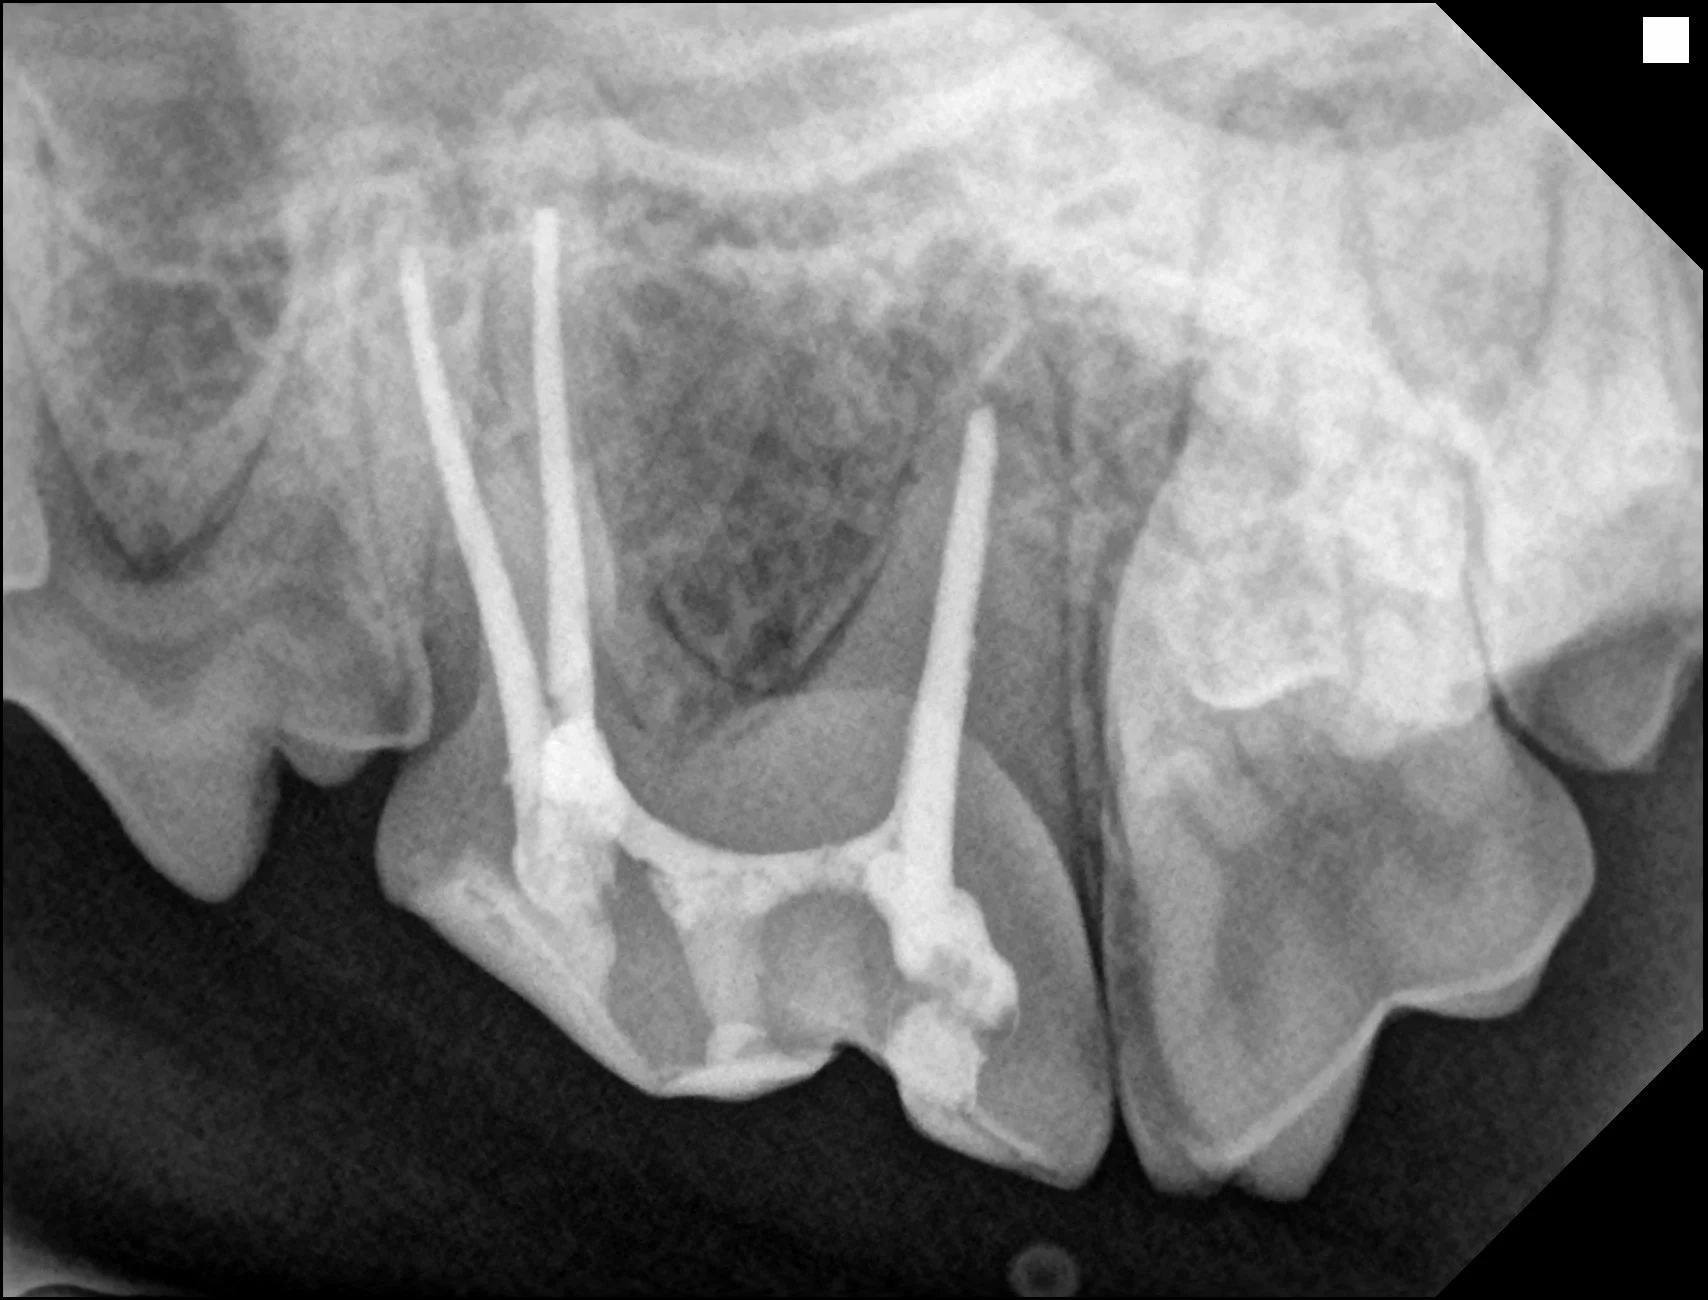

2. 시술 후 치과 방사선 확인​

동물의 신경치료는 한 번에 모든 과정을 완료해야 합니다. 신경치료 후에는 치과 방사선 촬영을 통해 결과를 확인합니다. 수술 당일 시술이 잘 되었다고 해도, 치료의 성공 여부는 3~6개월 후 치과 방사선 재촬영을 통해 확인해야 합니다.